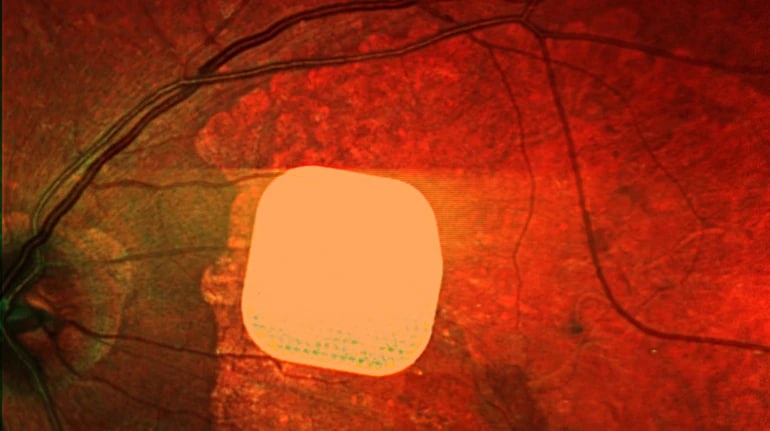

Британські лікарі успішно випробували новий електронний імплант Prima, який допомагає пацієнтам із макулодистрофією частково відновити зір. Цей мікрочип встановлюють під сітківку ока і з допомогою камери зчитують навколишнє зображення, яке передають на мікрочип. Після операції та періоду адаптації більшість учасників дослідження змогли розрізняти літери, цифри та слова. Лікарі підкреслюють, що ця технологія відкриває нові можливості для людей із важкими зоровими проблемами, допомагаючи покращити їхнє життя.